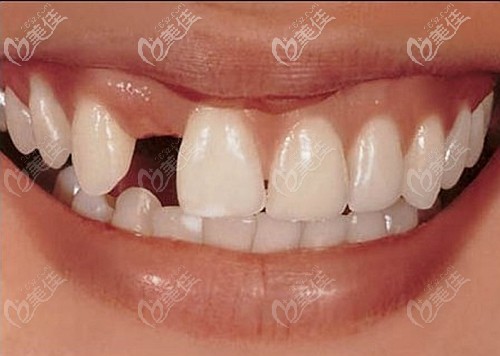

為什么大醫(yī)院不讓做馬里蘭橋?因為馬里蘭橋使用壽命短/后遺癥多/容易脫落被淘汰 b8250 G0 V0

為什么大醫(yī)院不讓做馬里蘭橋?莫非馬里蘭橋真的淘汰啦?其實大醫(yī)院不讓做馬里蘭橋是因為馬里蘭橋使用壽命短、后遺癥多、容易脫落等缺點,所以導(dǎo)致口腔醫(yī)院沒有馬里蘭橋修復(fù)項目。